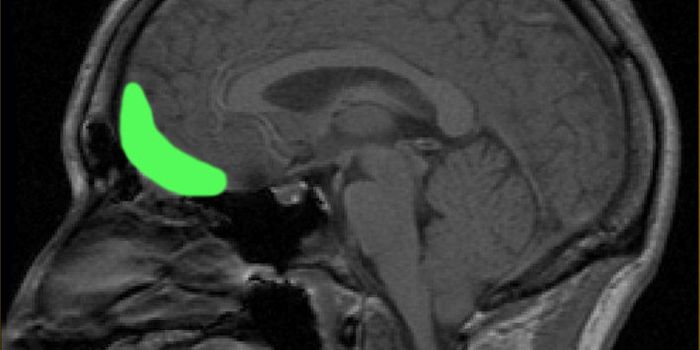

APR 15, 2015NeuroscienceSENIOR VOLUNTEERS WARD OFF BRAIN ‘SHRINKAGE'